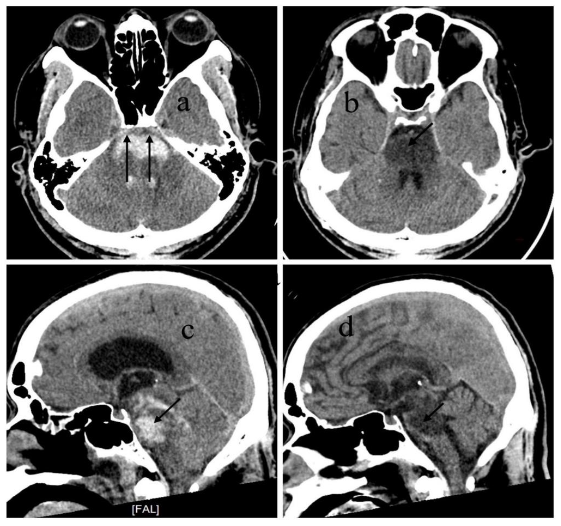

Follow-up CT or MRI was performed in the 3rd-4th week to exclude underlying lesions such as vascular malformations or tumors. The mRS was used to evaluate outcomes at week 4 and month 6. Special attention was given to anterior pontine involvement on initial CT scans. The hypothesis is complete involvement of the anterior pons was associated with poor recovery (vegetative state), while partial sparing correlated with better outcomes.

All 14 patients received comprehensive stroke care, including: strict blood pressure control (target SBP 140 mmHg), stabilization of vital signs, aggressive management of infections, ventricular drainage when obstructive hydrocephalus was present, early tracheostomy, prompt management of complications. Three patients died during hospitalization due to cardiac arrest associated with atrial fibrillation and failed resuscitation. Two patients with end-stage renal disease (ESRD) died from volume overload and related complications within the first week. Two surviving patients, who had complete ventral pons involvement, remained in long-term vegetative state despite aggressive treatment and absence of major comorbidities. Seven patients demonstrated partial sparing of the anterior pons on CT. These patients showed improvement in consciousness by week 4, responding to simple commands, and achieved partial functional independence by month 6. At 6 months: all 7 patients were able to communicate effectively. Motor recovery varied: some could ambulate with an ataxic gait, others required a wheelchair for mobility. All required daily assistance for activities of living.

Anatomically, the corticospinal tracts responsible for voluntary motor control are arranged ventromedial to dorsolateral within the pontine basis. In contrast, the cranial nerve nuclei and reticular formation, which control functions such as arousal, autonomic regulation, and coordination, are mainly located in the dorsal pons (tegmentum). When the hematoma completely involves the ventral pons, the corticospinal tracts are severely damaged, often leading to long-term motor deficits or a vegetative state, as seen in two patients in our series. However, when partial sparing of the ventral pons is present, as in seven of our cases, patients showed recovery of consciousness and meaningful motor function over time. These findings suggest that the most anterior part of the pons, which contains the corticospinal tract, is a critical region for predicting long-term outcomes in terms of motor coordination and the severity of motor deficits.

Our treatment decision framework is designed to assist emergency physicians and general practitioners who often face the responsibility of guiding patients families at the time of diagnosis. It integrates clinical and radiological criteria to determine the feasibility of active treatment. While massive ventral PPH generally carries a poor prognosis, our findings show that not all such cases result in death or vegetative state. Patients with no severe comorbidities and partial sparing of the anterior pons had a better-than-expected outcome, achieving communication, mobility with assistance, and some degree of independence.

Massive primary pontine hemorrhage is commonly associated with a poor prognosis. However, our case series demonstrates that functional recovery is possible in select patients. Specifically: Patients with partial sparing of the anterior ventral pons, and no severe comorbidities, showed significantly better outcomes than predicted. Total anterior pons involvement was associated with persistent vegetative state, even in otherwise healthy individuals. Further studies with larger sample sizes and prospective design are needed to validate these findings and refine the proposed decision-making framework.